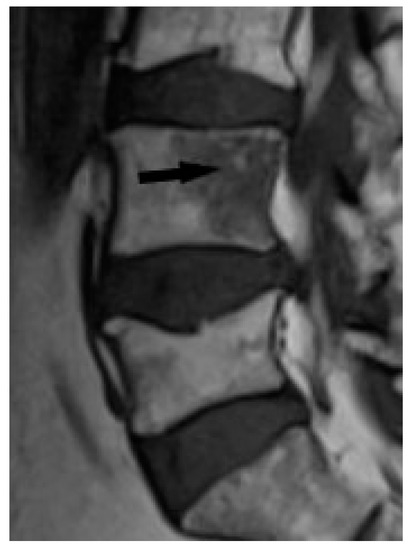

Figure 9. T1-weighted image. Hypointense lesion with irregular margins and with small foci of hyperintense fat (black arrow).

Bone marrow sarcoid foci are hypointense on T1-weighted images and hyperintense on T2-weighted and STIR image, with the same appearance as metastases, multiple myeloma or lymphoma [19] (Figure 8a,b). In T2-weighted images, lesions in sarcoidosis of the bone marrow may also show low and intermediate signal intensity, with signal being higher in STIR images [15].

The outlines of the lesions can be smooth or irregular, and sometimes the presence of normal fatty bone marrow within the lesion can be seen, which was thought to be an indicator of the benign nature of the lesion [15] (Figure 9). The presence of fat in the lesion may indicate involution. An additional differentiating feature may be the presence of a mass in the soft tissues, which is extremely rare in sarcoidosis, but more common in metastases [15].

However, differentiation between sarcoidosis and metastases may be difficult on a routine MR examination protocol. Moore et al. showed in an analysis of MR images of 34 patients with metastases and spinal sarcoidosis that it is not possible to differentiate between lesions based on routine MR images alone [15].